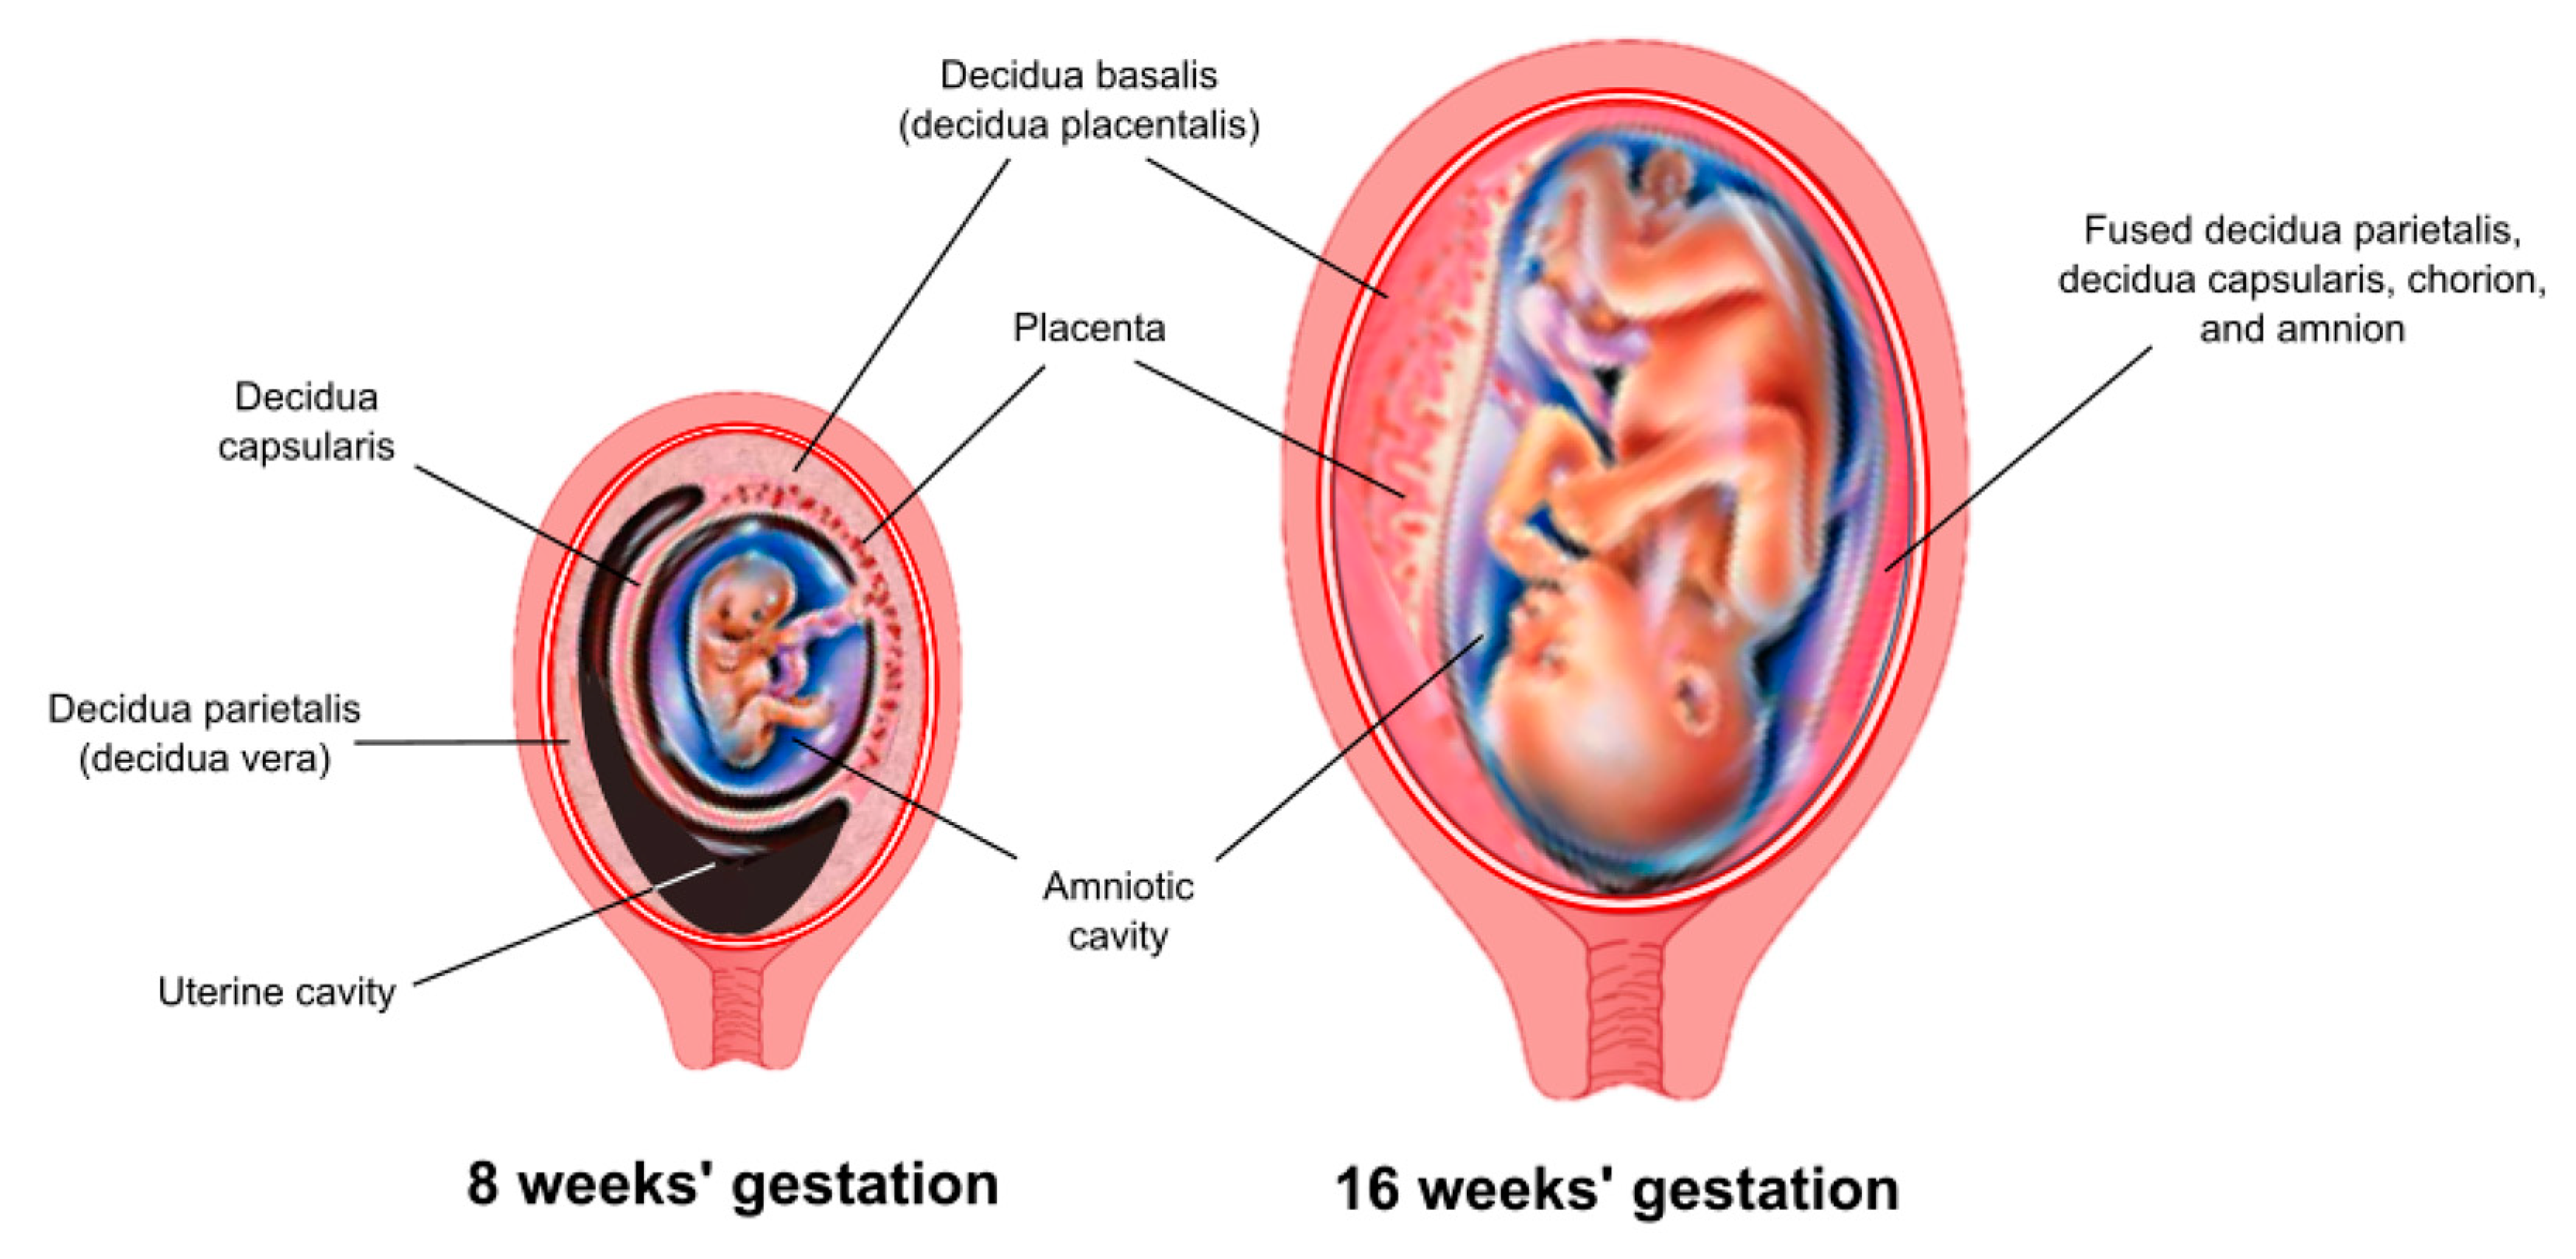

A. The Decidua

After fertilization, the corpus luteum in the ovary continues to function rather than atrophying, because of the influence of human chorionic gonadotropin (hCG), a hormone secreted by the trophoblast cells. This causes the uterine endometrium to continue to grow in thickness and vascularity, instead of sloughing off as in a usual menstrual cycle. The endometrium is now termed the decidua (the Latin word for “falling off”), because it will be discarded after the birth of the child.

The decidua has three separate areas:

Decidua basalis, the part of the endometrium that lies directly under the embryo (or the portion where the trophoblast cells establish communication with maternal blood vessels)

Decidua capsularis, the portion of the endometrium that stretches or encapsulates the surface of the trophoblast

Decidua vera/parietalis, the remaining portion of the uterine lining. As the embryo continues to grow, it pushes the decidua capsularis before it like a blanket. Eventually, the embryo enlarges so much that this action brings the decidua capsularis into contact with the opposite uterine wall (the decidua vera). Here, the two decidua areas fuse, which is why, at birth, the entire inner surface of the uterus is stripped away, leaving the organ highly susceptible to hemorrhage and infection